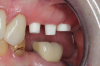

Fig 14. Final impression and cast.

Figure 14

Fig 15. Provisionals 12 weeks postoperatively.

Figure 15

After the preparations were evaluated and accepted by the clinician, provisionals were completed with traditional crown-and-bridge techniques. Then the provisionals were fabricated with a replication stent derived from the diagnostic wax up (Figure 14). The provisionals were well-fitted to both the natural dentition and the ceramic dental implants (Figure 15). The provisional that was fixed to the implant was kept out of occlusion and had a narrow buccal-lingual occlusal table. The smaller occlusal table and short occlusal scheme provided light loading forces and stimulated the bone tissuethe brain detects the stimuli and sends osteoblasts to the area to increase bone density surrounding the implant. The recommendation for the light-loading provisional phase was to have the patient function with the provisionals for 4 weeks.